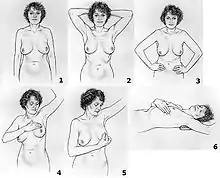

A clinical or self breast exam involves feeling the breast for lumps or other abnormalities. Medical evidence, however, does not support its use in women with a typical risk for breast cancer.[1]

Breast exam

Breast examination (either clinical breast exams (CBE) by a health care provider or by self exams) were once widely recommended. They however are not supported by evidence and may, like mammography and other screening methods that produce false positive results, contribute to harm. The use of screening in women without symptoms and at low risk is thus controversial.[7]

A 2003 Cochrane review found screening by breast self-examination is not associated with lower death rates among women who report performing breast self-examination and does, like other breast cancer screening methods, increase harms, in terms of increased numbers of benign lesions identified and an increased number of biopsies performed.[1] They conclude "at present, breast self-examination cannot be recommended".[1] There was no high quality evidence looking at clinical breast examination.[1]